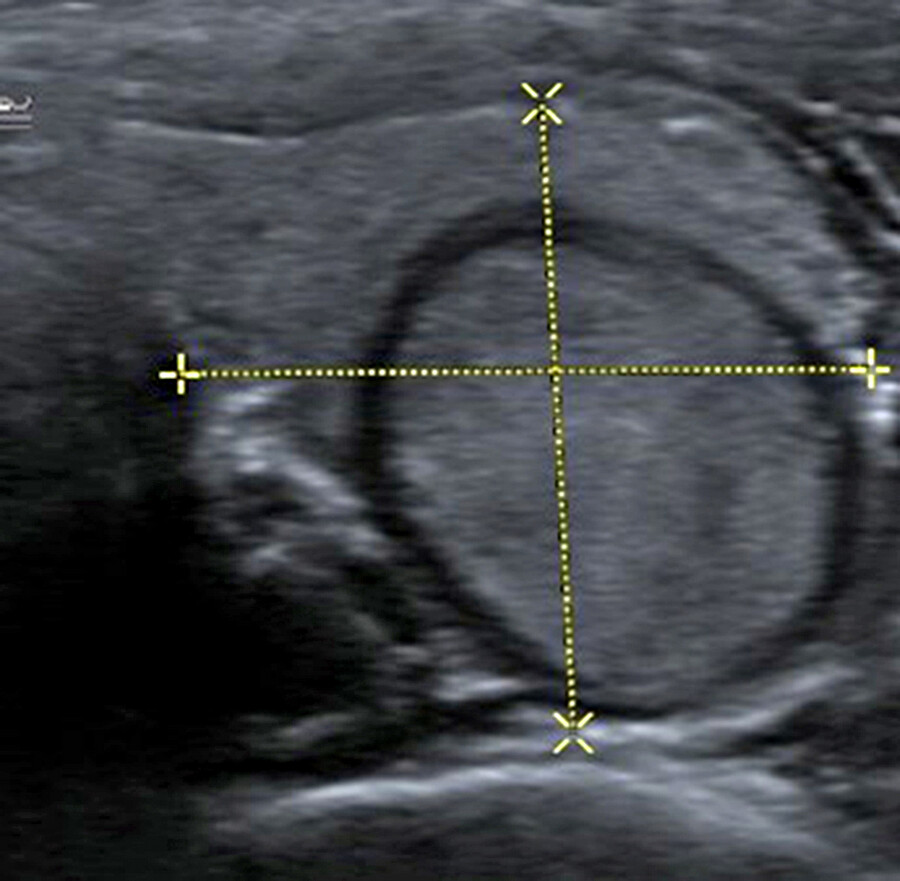

Sonographisch kann das Schilddrüsenvolumen durch Länge x Breite x Dicke x 0,5 gut bestimmt werden. Die obere Grenze des Schilddrüsen-Volumen liegt zwischen 18ml bei der Frau und etwa 25ml beim Mann. Aufgrund bestimmter Malignitätskriterien die jeder Sonographeur kennen sollte, erfolgt zur weiteren Abklärung in der Regel zusätzlich eine Schilddrüsen-Szintigraphie mit Technetium-99m-Pertechnetat, wobei die Radionuklid-Aufnahme in die Schilddrüse gemessen wird. Dadurch kann die Lage, Form und Größe der Schilddrüse bestimmt, sowie bei starker Speicherung dieses als Hinweis auf einen warmen Knoten oder bei Nicht-Speicherung oder kaum eine Speicherung als kalten Knoten (Krebsverdacht) oder bei intensivster Speicherung (Heißer Knoten) als autonomes Adenom gewertet werden.

Wichtig ist: Ein kalter Knoten der sonographisch echofrei ist, entspricht in der Regel einer Zyste. Ein kalter Knoten, der nicht echofrei ist, ist krebsverdächtig (etwa 4%). Der Karzinomverdacht muss daher weiter abgeklärt werden. (Abb. 4 und Abb. 5)